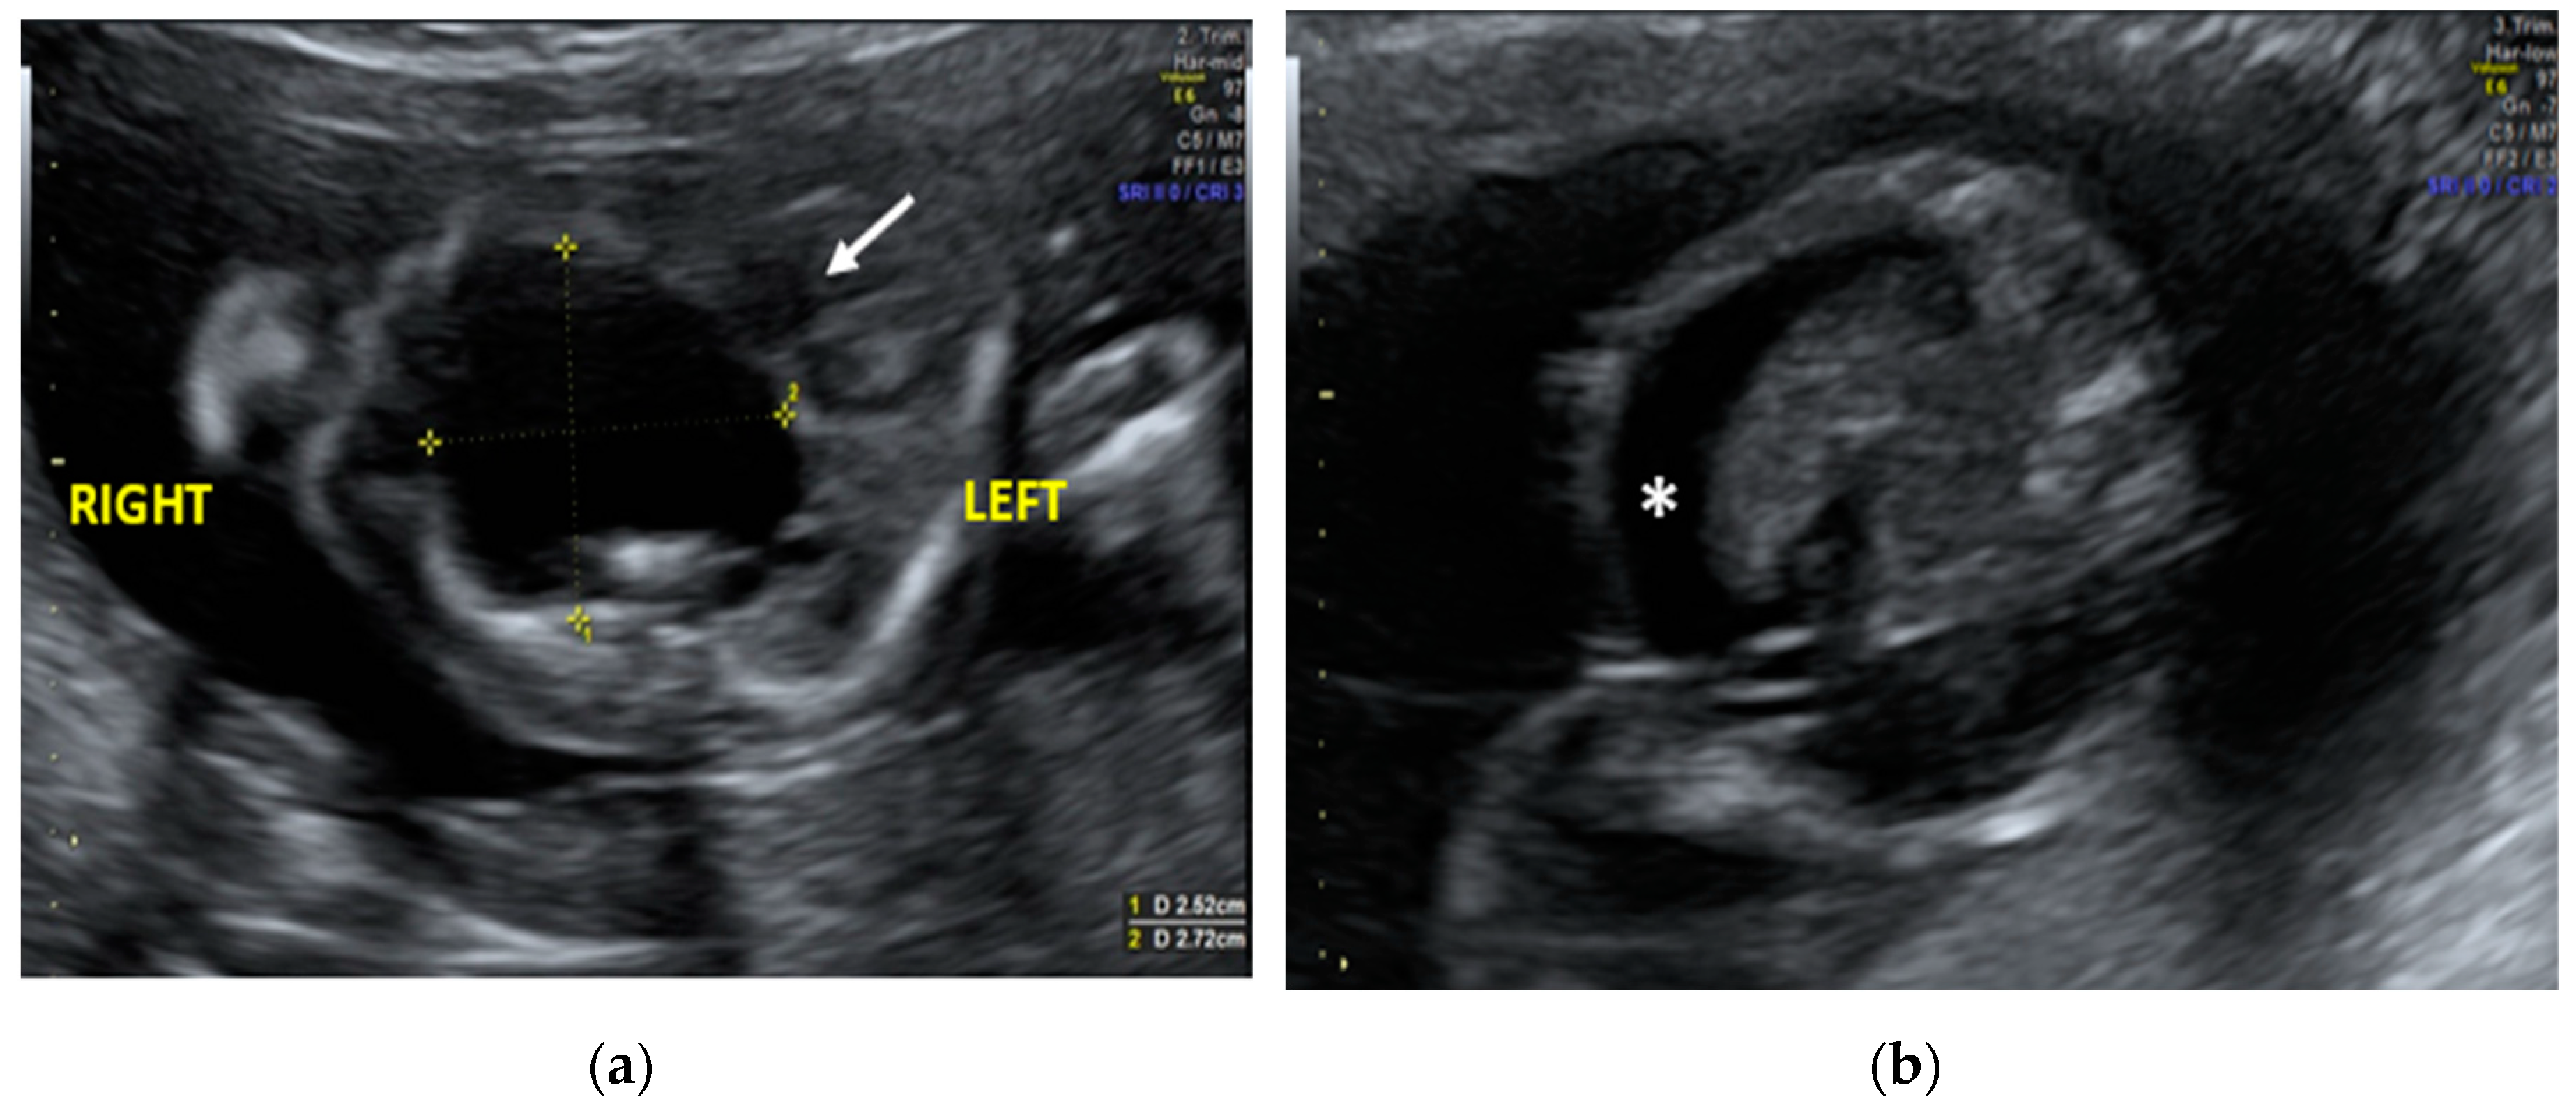

2. Case report